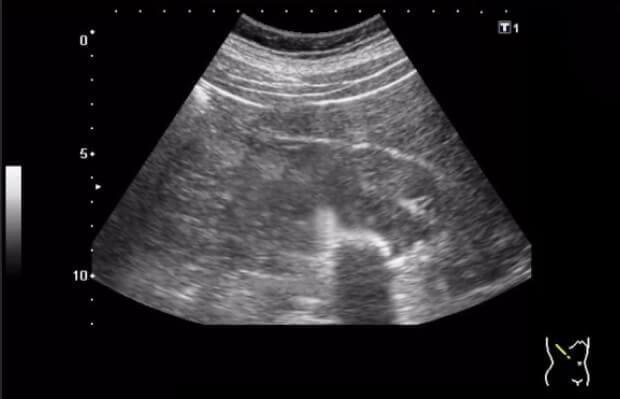

Egy hónap alatt az ultrahang kimutatta, hogy a ciszta kétszer zsugorodott - 20 mm-ről 10 mm-re! És a három kő közül kettő megolvadt és előkerült (Emlékszem, hogy ez előtt pár nappal fájt a vizelés). Aztán áttértem a normál adagra. Egy hónappal később az orvos megdöbbent, amikor ultrahangot végzett - a vesék tiszták voltak! emoji emoji emoji

before előtt

after után